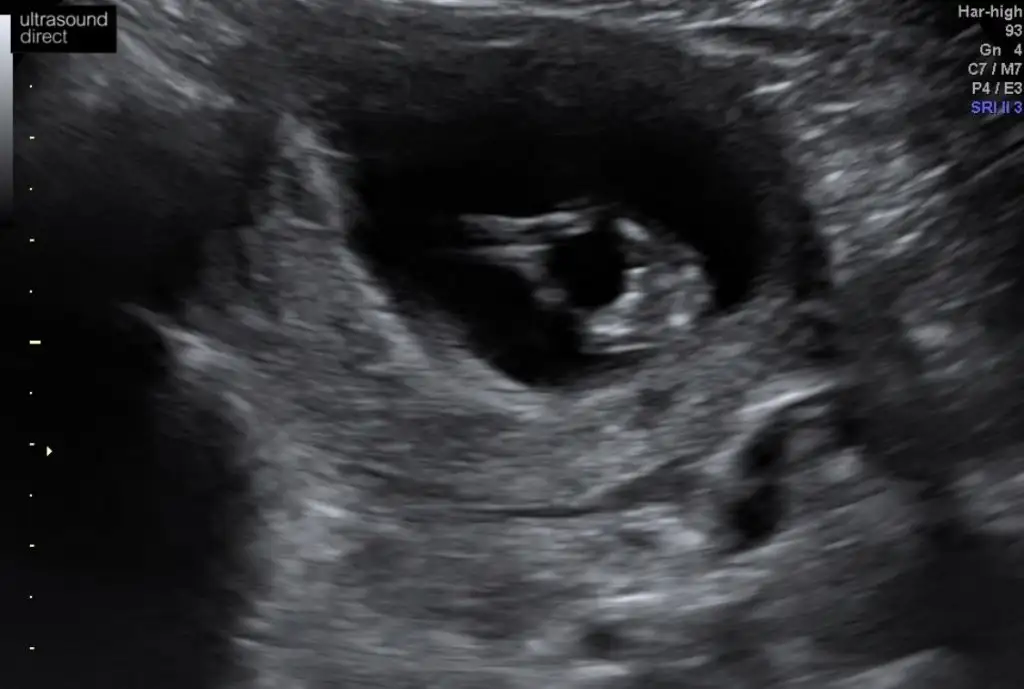

Daha önce ne dedim bilmiyorum burada nub paralel görünüyor kız gibi 12+ usg olursa paylaşınEki Görüntüle 2574907 Eki Görüntüle 2574908 Eki Görüntüle 2574909 Canım 11+1ız sabah dayanamadık doktora gıttık.cınsıyetı bellı degl ama eşim cok merak edıyor sor bakalım dıyor nub a göre neymıs cınsıyetı dıyebıze tekrar bakarsan cok sevınırım

Daha önce erkek demıstınız ama o zaman 10 haftalıktı.12.haftayı paylaşacağım cok teşekkürlerDaha önce ne dedim bilmiyorum burada nub paralel görünüyor kız gibi 12+ usg olursa paylaşın

11 yada 12 hafta tekrar paylaşırsınız şimdilik erkek ama 12 hafta tahminimi onaylarız

Erkek olduğunu tahmin ediyorum